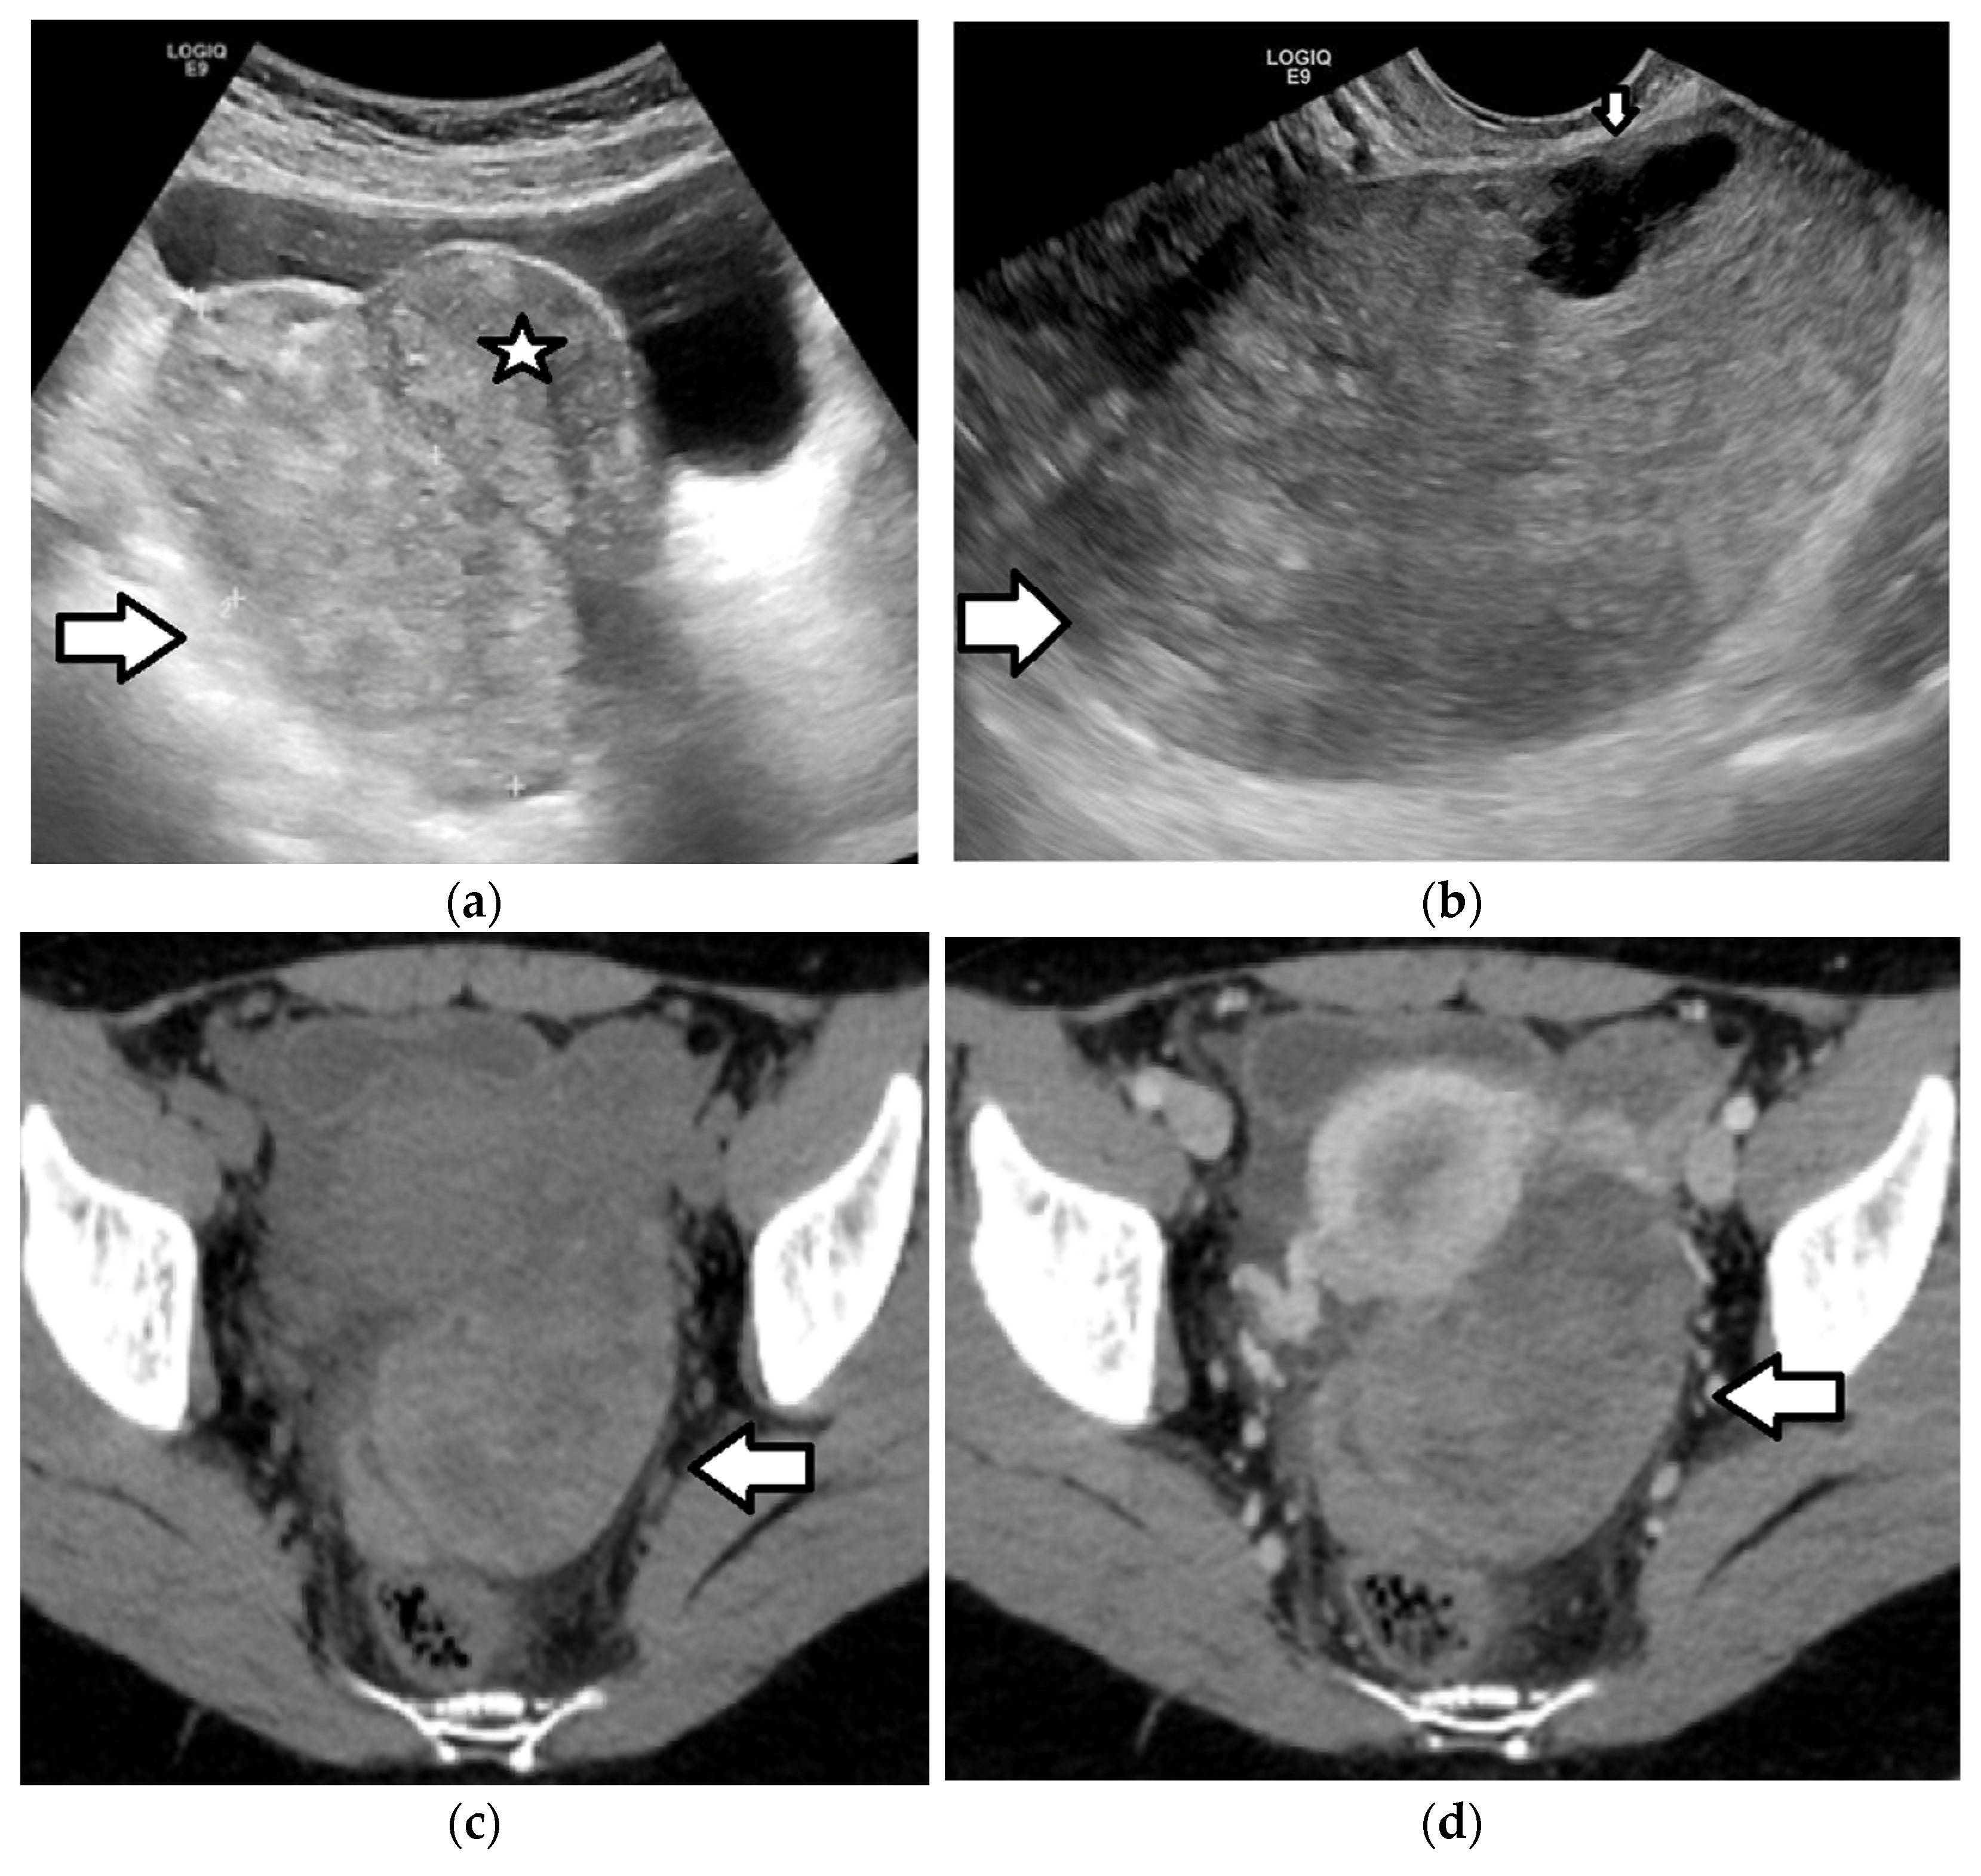

| Benign epithelial tumors: serous, mucinous, and mixed cystadenoma | Most common (47–58%) of epithelial tumors After menarche | Benign Recurrence: rarely in contralateral ovary | Serous cystadenoma: unilocular or multilocular, homogeneous, cystic tumor with serous fluid, absence of internal vascularity on Doppler US, and contrast enhancement on CT/MRI, except for thin, smooth walls or septa (≤ 3 mm) Mucinous cystadenoma:multilocular cystic tumor, large size, absence of internal vascularity on Doppler US, and contrast enhancement on CT/MRI, except for thin, smooth wall or septa (≤3 mm), and presence of mucinous fluid, with higher than water CT density (>20 HU) and high T1 signal (proteinaceous content); “stained glass” appearance:different signal intensity in the cystic parts of the tumor due to variable concentrations of mucin and hemorrhage as a characteristic finding | |

| Borderline and malignant epithelial tumors | Borderline: 21–38% of epithelial tumors, and more common in children and young women compared to in adults Malignant: rare (<5%) | Borderline: may recur (7.7%) Malignant: early-stage and low-grade | Large size, bilateral masses, cystic-solid tumor, with solid, vascular components, thick and irregular walls and septa, and/or papillary projections, with blood flow on Doppler US and enhancement on CT/MRI, as well as solid tumor with areas of necrosis Ancillary findings: pelvic organ or pelvic sidewall invasion, ascites, peritoneal metastases Papillary projections: intermediate T1 and T2 signal, variable vascularity, and may have a central hypointense fibrovascular stromal core and hyperintense periphery on T2WI, which are mostly characteristic of borderline tumors |